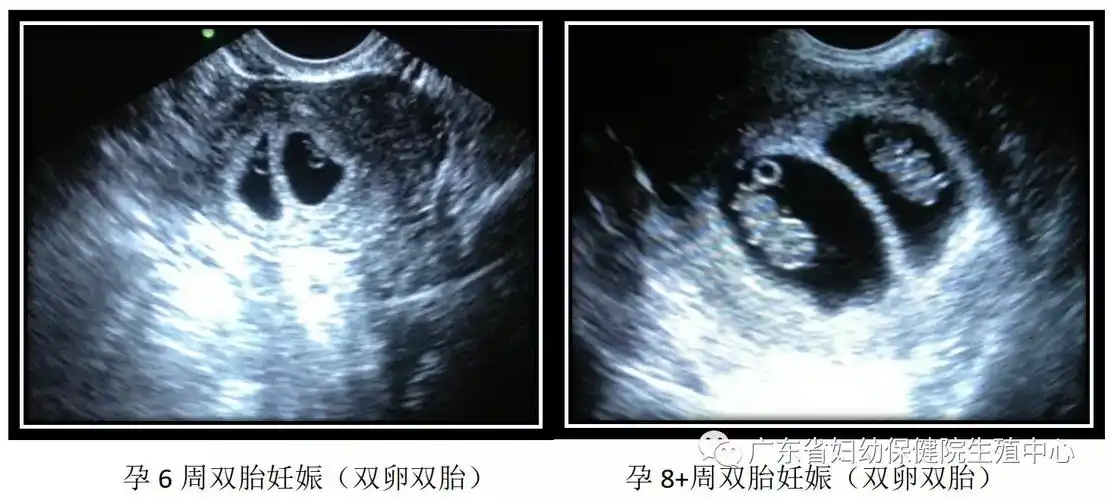

如一个孕囊内有两个卵黄囊及两个胚芽,则为单卵双胎附:早期妊娠天数及

如果是异卵双胞胎,因为它有两个胎囊,需要等胚胎出现胎心和胎芽,也就

50天早孕双胎妊娠(双孕囊)